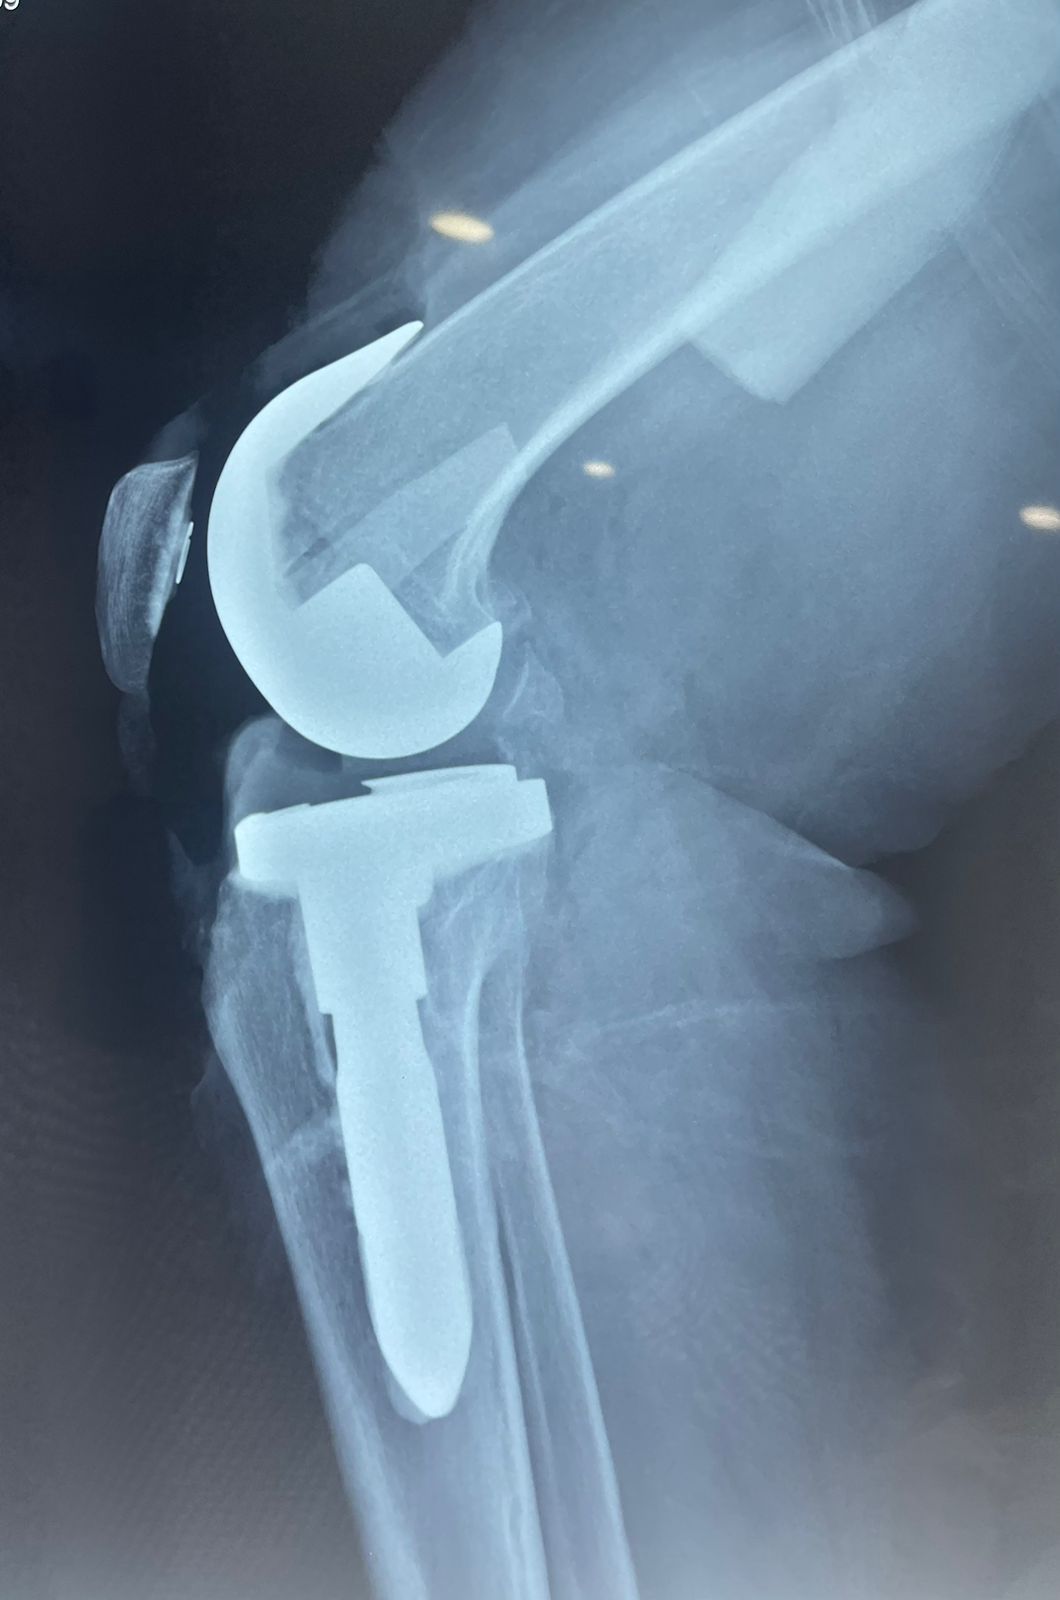

Fotos y videos